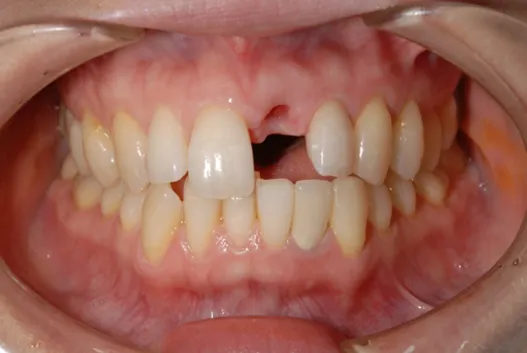

初診時

| 患者様のお悩み | 外傷で歯が抜けた |

|---|---|

| 治療法・使用素材 | インプラント治療の後、セラミック治療 |

| 患者様の年代 | 20代 |

| 治療開始年齢 | 20代 |

| 治療にかかった期間 | 8か月 |

| 性別 | 女性 |

| この治療のリスクについて | インプラントが正しい位置に入るかどうか |

| 治療にかかった費用 | 45万円 |